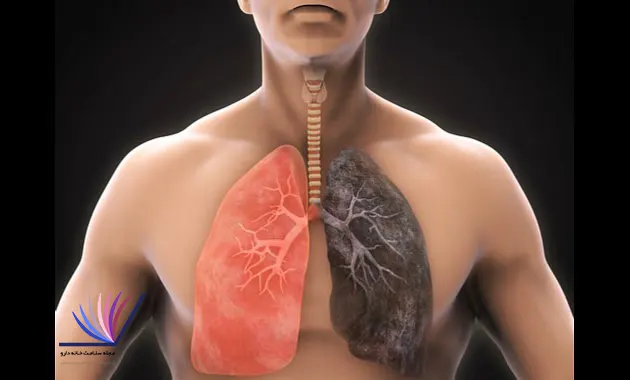

همه ی ما آگاه به تاثیر دخانیات روی بدن و دستگاه های مختلف آن هستیم و همیشه برای ما گفته شده است.با این حال آن را مورد بررسی قرار می دهیم که شاید از مصرف آن اجتناب کنیم.مواد شیمیایی که در دخانیات وجود دارد بیشترین تاثیر منفی بر روی سیستم تنفسی بدن ما می گذارند.

در حال حاضر، میدانیم که تاثیر دخانیات منجر به بروز مشکلات جدی سلامتی سیستم تنفسی میشود. از جمله این مشکلات میتوان به بیماریهای مزمن مانند بیماریهای ریه، آسم، برونشیت مزمن، و حتی سرطان ریه اشاره کرد. بنابراین، شناخت کامل از تأثیرات دخانیات بر سیستم تنفسی ضروری است تا افراد بتوانند خطرات آن را درک کرده و اقدامات لازم برای جلوگیری از اثرات منفی آن را انجام دهند.

مواد شیمیایی موجود در دود و تنباکوی سیگار باعث تحریک مجاری تنفسی،کاهش خاصیت ارتجاعی بافت ریه و تخریب دیواره های ریه می شود که از مهترین تاثیر دخانیات به خصوص سیگار است.

مواد سرطان زا و قطران که در تنباکو وجود دارد به تشکیل سرطان کمک می کند،که در ابتدا سرطان ریه نهفته است؛هنگامی که علائمی مثل سرفه خونی،مشکل در تنفس به وجود می آید حتما باید پیگیری شود.

سیگار کشیدن اثرات ویران کننده ای بر روی ارگان های داخلی بدن مثل:ریه و قلب می شود.